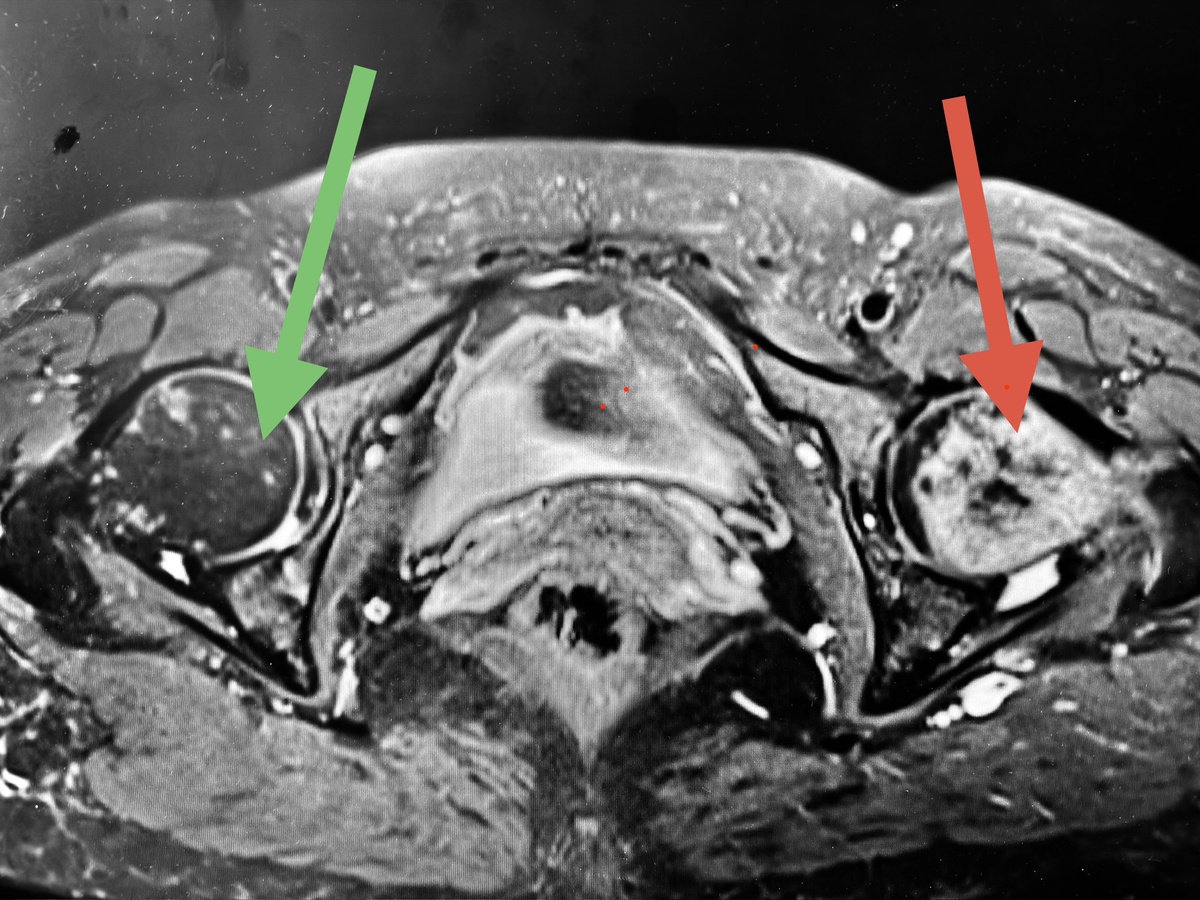

Что, вы думаете, оказалось на МРТ? Правильно - некроз головки и шейки бедренной кости:

Белая кость - некроз. Тотальный. На фоне полного здоровья. КОВИД был - в легкой форме, несколько раз, давно. А некроз - сейчас. Никаких других причин выявить не удалось.